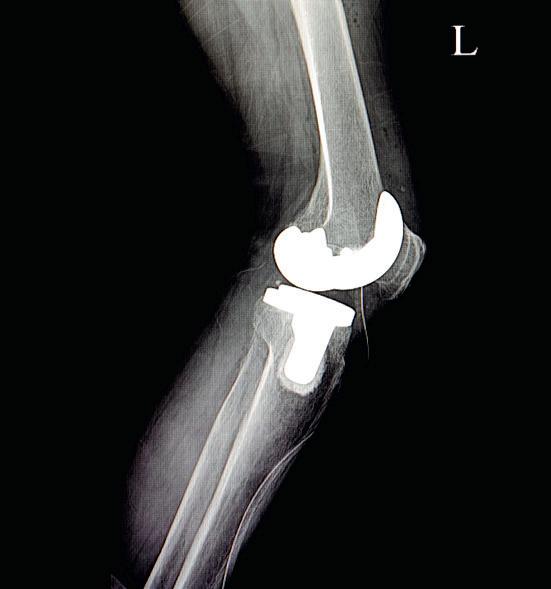

104 Hip, Hop, Don’t Stop

Is hip pain slowing you down? Replacing a painful joint is becoming faster and easier as medical technology improves